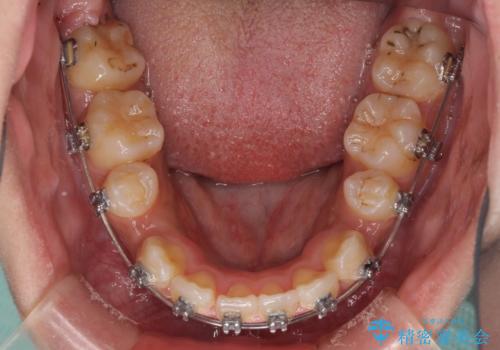

- メタルブラケット

- 2年1ヶ月

上下前歯部叢生のスペース獲得のため、上下顎左右小臼歯各1歯(計4本)と全ての親知らずを抜歯して、矯正治療を行うこととしました。

上下の正中位置が大きくずれていたため、治療期間の長期化や正中が合わないまま終了することが予想されましたが、思っていた以上にスムーズに歯が移動し、満足いただける仕上がりとなりました。